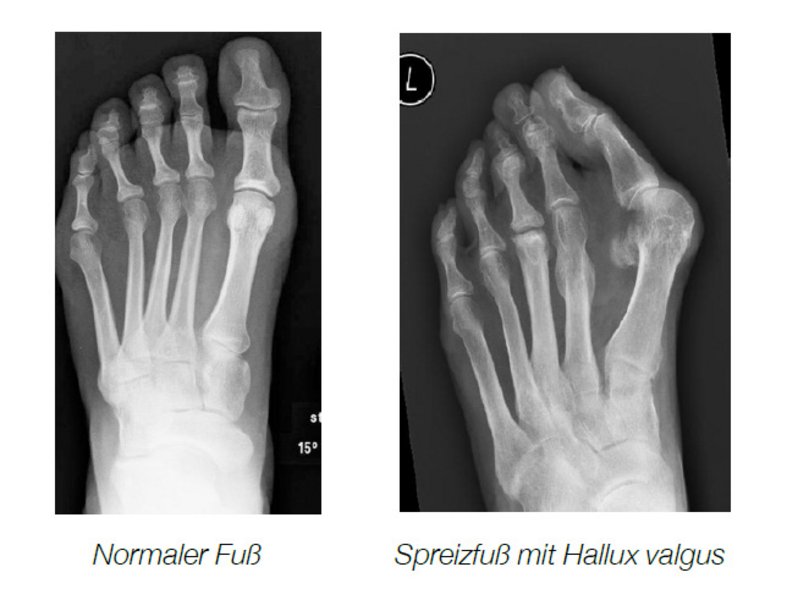

Durch eine Abweichung des ersten Mittelfußknochens nach innen kommt es zu einer Abweichung der großen Zehe nach außen. Die Sehnen der Zehe verlaufen nicht mehr zentral über das Gelenk sondern seitlich und ziehen die Zehe in die falsche Position.

Notwendig ist eine exakte Diagnose der Fehlstellung!Der Fuß muss angesehen, angefasst und geröntgt werden. Röntgenbilder in mehreren Ebenen unter Belastung sind notwendig. Häufig

muss zusätzlich ein Ultraschall und eine Fußdruckmessung durchgeführt werden.